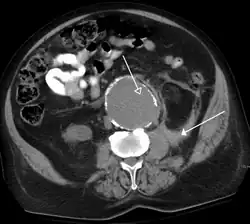

-

FIGURE 7. Selected images from a renal mass specific protocol CT. Corticomedullary phase (axial 7a) demonstrates peripheral enhancement of the renal cortex with minimal opacification of the renal medulla. There is a large renal cell carcinoma in the left kidney (right in image) which can be differentiated from the normal renal parenchyma by the heterogeneous and differential enhancement. The renal artery and vein are opacified in this phase as well. The collecting system is not opacified (coronal reformat 7b). In the parenchymal phase, the renal cortex and the medulla are enhancing. The renal cell carcinoma in the left kidney is not as well defined when compared to the corticomedullary phase images, but is actually slightly more conspicuous. There is some contrast noted within the collecting system during this phase (7c).